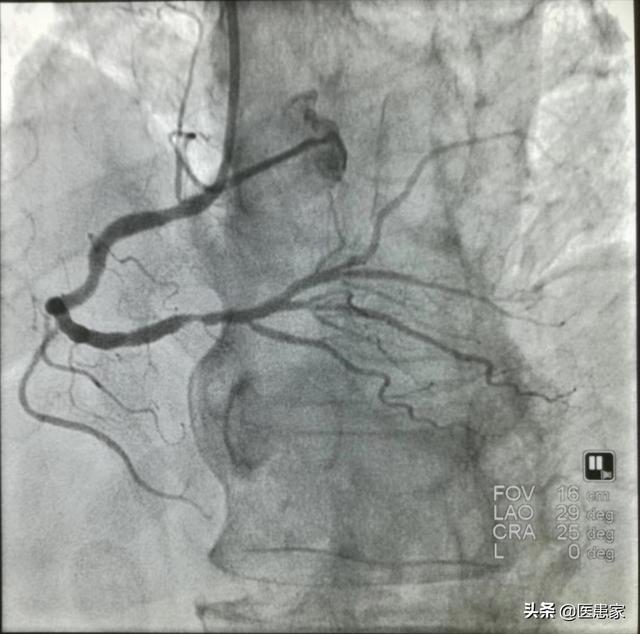

冠動脈は心臓の血液供給システムである。 正常な状態では、冠動脈は2本、すなわち左冠と右冠であり、左冠は前下行枝とエコー源枝の2つの枝に分けられ、右冠は動脈円錐枝、右縁枝、洞房結節枝、房室結節枝、後室間枝などの主要な枝を送り出し、前下行枝は動脈円錐枝、後中心枝、心室中隔間枝などの主要な枝を送り出す。これらの冠動脈はすべて心臓に血液を供給し、心臓の一定の領域に血液を供給することで、心臓の作業細胞や自己調節細胞に十分な血液が供給されるようにし、その結果、心臓は正常なリズムと速度で拍動することができる。

冠動脈狭窄は4つのグレードに分類することができ、25~49パーセントの狭窄をグレード1の狭窄、50~74パーセントの狭窄をグレード2の狭窄、75~99パーセントの狭窄をグレード3の狭窄、グレード4の狭窄を100パーセント、すなわち血管が完全に閉塞した状態を心臓発作と呼ぶ。

冠動脈狭窄が70%以上の二次狭窄、つまり中等度の狭窄は、理論的に言えば、まだ狭窄の第三度に達していないので、冠動脈ステントを埋め込む必要はない。しかし、注意しなければならないことが一つある。冠動脈狭窄の危険性は、主に病変の場所に依存する。例えば、病変の左主幹は非常に危険で、医師はしばしばそれを「未亡人の枝」と呼ぶ。左心室の血液供給の大部分は左主幹から来て、この部分の血栓や閉塞の形成はしばしば致命的で、患者が死亡する原因となり、例えば、冠状動脈の閉塞の洞結節や房室結節の供給は、深刻な不整脈や致命的な原因となり、末梢血管の閉塞であれば、比較的害が少なくなります。

冠動脈疾患の治療は、原則として保存的治療、すなわち内服薬による治療や生活習慣の改善などを優先し、保存的治療が無効な場合にのみ冠動脈ステント留置術や冠動脈バイパス移植術などの外傷的治療が選択される。

まとめると、70%以上の冠動脈狭窄の重症度は病変の位置によって異なり、ステントを留置する必要がある場合は、医療専門家に相談して最善の治療法を選択することが推奨される。